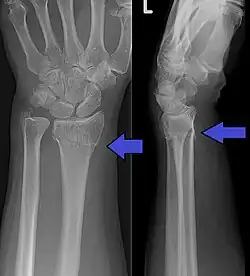

Fracture de Pouteau-Colles

Une fracture de Pouteau-Colles est une rupture osseuse, avec déplacement dorsal, du radius (situé dans l'avant-bras). Elle se caractérise par un déplacement du poignet et donc de la main.

Elle désigne la fracture de l'extrémité distale (loin de l'épaule) du radius avec déplacement dorsal et radial, ainsi qu'une bascule postérieure. La rupture de l'os se situe à proximité de l'articulation radio-carpienne (en général entre 2 et 5 cm).

- De face : trait simple, transversal, sus articulaire, métaphysaire.

- Bascule externe de l'épiphyse radiale.

- Horizontalisation de la ligne bi-styloïdienne.

- De profil : bascule postérieure épiphyse radiale.